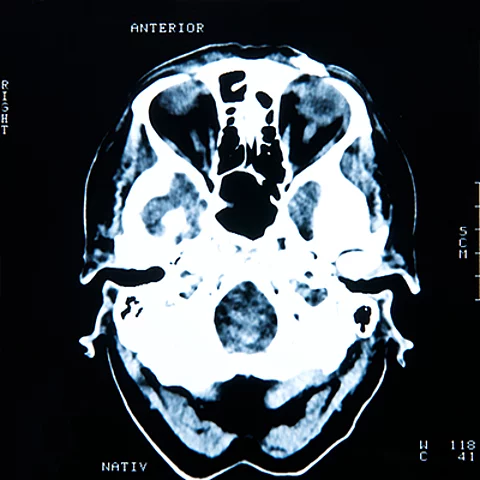

Um schonend operieren zu können, ist das Wissen um die exakte Tumorart unerlässlich. Doch nicht immer verfügen Chirurgen vor der Operation über gute Kenntnisse über den genauen Tumortyp. Mithilfe künstlicher Intelligenz kann eine genetische Analyse während der Operation erfolgen, wie die Ergebnisse einer niederländischen Studie zeigen.

Icruci/tondruangwit/stock.adobe.com_edited by Thieme